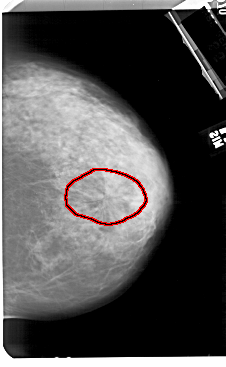

A_1504_1.RIGHT_CC

RIGHT_CC LINES 5491 PIXELS_PER_LINE 3376 BITS_PER_PIXEL 12 RESOLUTION 43.5 OVERLAY

FILE: A_1504_1.RIGHT_CC.OVERLAY

TOTAL_ABNORMALITIES 1

ABNORMALITY 1

LESION_TYPE MASS SHAPE ARCHITECTURAL_DISTORTION MARGINS SPICULATED

ASSESSMENT 5

SUBTLETY 3

PATHOLOGY MALIGNANT

TOTAL_OUTLINES 1

BOUNDARY